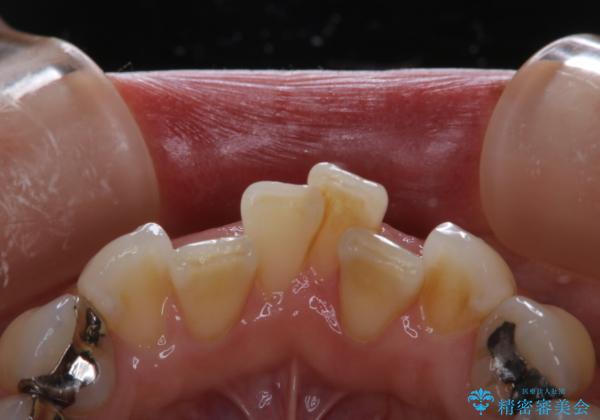

矯正治療の開始前にPMTCで汚れの除去

- これから矯正治療が開始される方です。装置の作成前にクリーニングを希望とのことでした。PMTC30分コースを行いました。

プラーク(細菌の塊)や歯石がたまると歯の表面はザラつきいてきます。そのザラつきは歯周病や虫歯菌の棲家となります。そのまま放置すると、歯肉が腫れてきたり、歯肉から出血したり、口臭が強くでたりします。とくに歯肉の境目は、歯磨きで汚れを除去することが難しく、プラーク(細菌の塊)や歯石が溜まりやすい場所です。

歯並が、がたついている場合はなおさら汚れが溜まりやすいです。矯正治療前や定期的にPMTCをすることで、矯正治療中の歯肉トラブルを防ぐことにつながります。